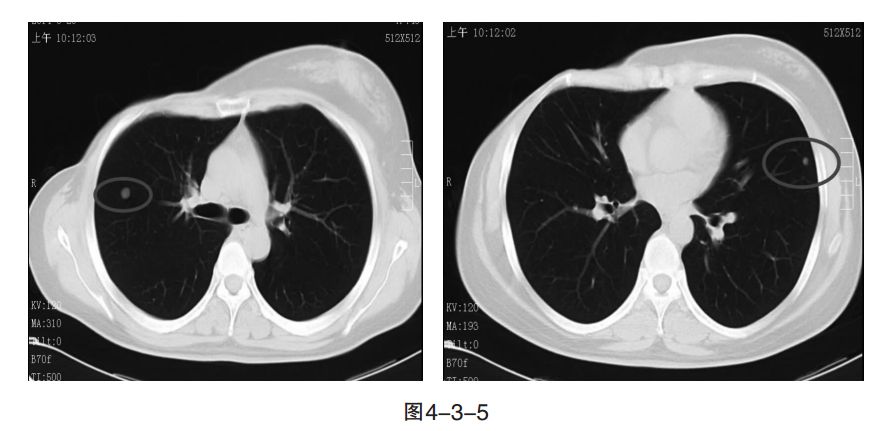

病情变化:2014 年6月,复查CT提示,肺内新发转移灶(图4-3-5),病情进展。

Q、如何明确肺内再次出现的新病灶来源什么?

患者左肺下叶原发肺腺癌未进展,提示从TKI中持续获益,应继续TKI治疗。肺内新发病灶相对较小,穿刺成功率低,可以考虑再次行穿刺活检明确新发病灶病理来源。

患者拒绝再次活检,考虑患者为肺癌、乳腺癌双重癌,左肺腺癌经EGFR检测示19外显子突变,经TKI治疗后左肺下叶原发灶疗效PR。经GT化疗方案2个周期,疾病进展,肺内出现新病灶。